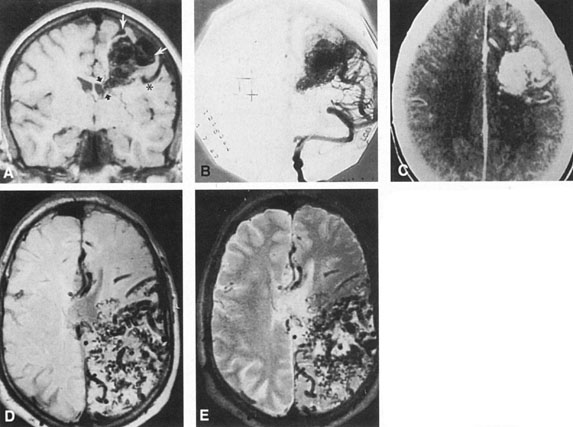

SUPRATENTORIAL

From 85% to 90% of AVMs are in the supratentorial compartment and are supplied primarily by the carotid circulation (Figs. 7 and 8). The remainder are supplied by the vertebrobasilar system. The approximate frequency of location is as follows: frontal, 22%; temporal, 18%; parietal, 27%; occipital, 5%; and deep intraventricular or paraventricular, 18%. The intracerebral site of the malformation does not necessarily indicate that there will be signs referable to that area simply from the mass effect of the malformation. Clinical features primarily result from subarachnoid hemorrhage or intraparenchymal hemorrhage with hematoma formation.

Fig. 7. Supratentorial arteriovenous malformation in a 28-year-old woman with a history of focal motor seizures for many years and a recent subarachnoid hemorrhage. A: Lateral projection carotid arteriogram demonstrating a huge deep hemispheral arteriovenous malformation. B: Frontal projection. C: Fundus photograph showing anomalous tortuous vasculature in each eye. No retinal arteriovenous shunt was detectable.

Fig. 8. Multiple supratentorial arteriovenous malformations (AVMs). A: Lateral projection of left carotid arteriogram shows dilated afferent artery (solid arrow) feeding the right hemispheric parietal AVM (open arrow). B: Right carotid injection fills a second, more posteriorly located, parietooccipital AVM (open arrow), which drains immediately to markedly dilated cortical veins (curved arrow).

In general, when hemorrhage occurs involving a portion of the visual radiations, a homonymous visual field defect is to be expected. Selective involvement of the anterior visual pathways may occur either with extensive venous angiomas at the base of the brain or as part of the Wyburn-Mason syndrome (see later), with direct involvement of the optic nerve, chiasm, or tract. Other variants such as congenital cavernous hemangiomas may involve the anterior visual pathways,68 as may intraparenchymal cryptic AVMs69 and present as symptomatic visual loss also resulting from hemorrhage and hematoma. Amaurosis fugax may even be the presenting symptom of supratentorial AVMs when blood is shunted to the meningeal circulation from the ophthalmic artery.70 When supratentorial AVMs drain into dural venous sinuses or the vein of Galen, distant ocular effects evolve, such as proptosis71 or ophthalmoplegia72 because of arterialization of cavernous sinus complex.

Of particular interest are those AVMs that involve the occipital lobe (Fig. 9). The clinical differentiation of migraine from a cerebral AVM was previously regarded as difficult because the clinical features of occipital lobe AVMs include visual phenomena or headaches. However, in most cases the clinical distinction is possible. In 26 cases with occipital AVM, two distinct syndromes were defined in 18 patients: occipital epilepsy and occipital apoplexy.73 Focal seizures with occipital malformations consist of elementary visual sensations similar to the phenomena evoked by direct cortical stimulations. When seizure activity occurs in the striate cortex (area 17), the patient usually reports sensations of moving lights in the right or left homonymous fields. The sensations are poorly formed, episodic, usually brief, sometimes colored, and unassociated with the angular, scintillating figures so characteristic of migrainous cortical phenomena. Epileptic discharges from areas 18 and 19 cause photopsias that are unlikely to remain stationary and to flicker rapidly. The epileptic photopsias usually last only seconds; occasionally they last for a few minutes before the onset of a generalized seizure. In other instances only the brief visual episodes occur without spreading to produce a generalized seizure. Momentary dimming or blindness in one or both homonymous fields may be experienced with seizure activity in the occipital areas.

Fig. 9. Carotid arteriogram of an occipital lobe arteriovenous malformation (AVM). Lateral (A) and frontal (B) projections demonstrating a small occipital AVM (arrow). The patient was a 23-year-old woman who presented with severe apoplectic unilateral headache, total left homonymous hemianopia, and mild nuchal rigidity. Despite xanthochromic cerebrospinal fluid, she was initially diagnosed elsewhere as having migraine. An AVM was successfully resected, and a small occipital lobe hematoma was removed.

Occipital apoplexy results from hemorrhage and hematoma formation within the occipital lobe and is characterized by sudden severe headache and homonymous visual field loss. Homonymous hemianopia is the most important sign produced by vascular malformations of the occipital lobe. Compression and necrosis of visual pathways by an intracerebral hematoma are the principal mechanisms. Usually the hematoma is large and tends to split or dissect longitudinally through the white matter of the occipital lobe. The effects of compression may be reversed by prompt, surgical evacuation of the hematoma.73 With hemorrhage into one occipital lobe, hemianopia in the visual field of the contralateral normal occipital lobe may develop, producing total blindness that can last for several days. The rapidly expanding hematoma may shift the damaged hemisphere anteriorly, or across the midline, with downward herniation of the uncus through the tentorial incisura. This shift compresses the posterior cerebral arteries and accounts for bilateral occipital lobe dysfunction. Arrest of function in the undamaged occipital lobe may be due to an interhemispheral inhibitory phenomenon termed diaschisis. Visual field defects with occipital AVMs are regularly due to hemorrhage and hematoma formation. Congenital arteriovenous malformations can occupy the entire occipital pole (the macular projection area) for decades without producing visual field defects.

Although migraine is often cited as a symptom of AVM, it is extremely rare that classic migraine is mimicked by occipital AVM. None of the patients in the series by Troost et al73 described the 15- to 20-minute episodes that characterize the visual aura of classic migraine. The headaches of AVM differ from migraine in that they are constantly localized to the same side of the head, and intermittent visual phenomena, if present, can persist throughout the headache or even after, whereas in migraine the visual phenomena usually precede the headache. Bruyn74 has reviewed the clinical features of 57 reported and 7 personal cases of AVM, concluding that the migraine of AVM is late onset, nonfamilial, and brief. Rarely, the complete clinical symptomatology of classic migraine can be mimicked by an occipital lobe AVM (see Chapter 16).75 In addition to hemianopia, other visual disturbances can occur after hemorrhage into the occipital lobe, including alexia without agraphia (see Chapter 7).